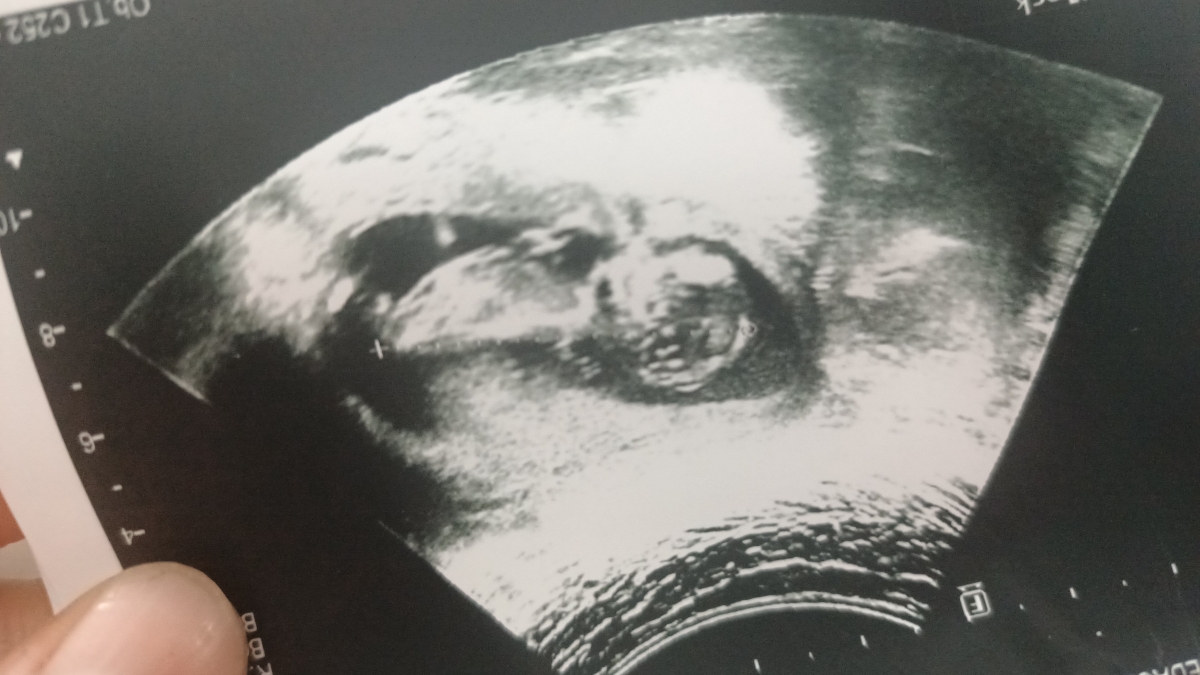

بنظرتون نی نی پسره یا دختر؟

تشخیص جنسیت از روی سونو ان تی

منم میگم پسر احتمالا

آخه جمجه اش با دخترم فرق داره

یکی از راه هاش همین جمجه اس

جمجه دخترا گرده

پسرا گرد نیس

آخه جمجه اش گرد نیس مث دخترا